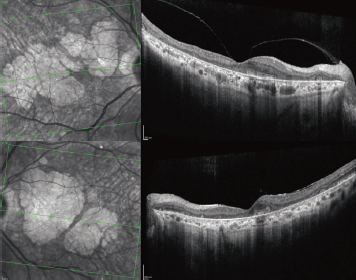

Fundus autofluorescence demonstrated dense peripapillary and central hypoautofluorescence surrounded by drusen and normal vessels (Figure 1 C, D). The periphery was notable for reticular changes with speckled hyper- and hypoautofluorescence. Optical coherence tomography showed an abnormal foveal contour and large areas of outer retinal atrophy adjacent to drusen deposits. No associated intraretinal or subretinal fluid was present (Figure 2).

Figure 2. Optical coherence tomography of the right (top) and left eyes show geographic atrophy and dense drusenoid deposits. |